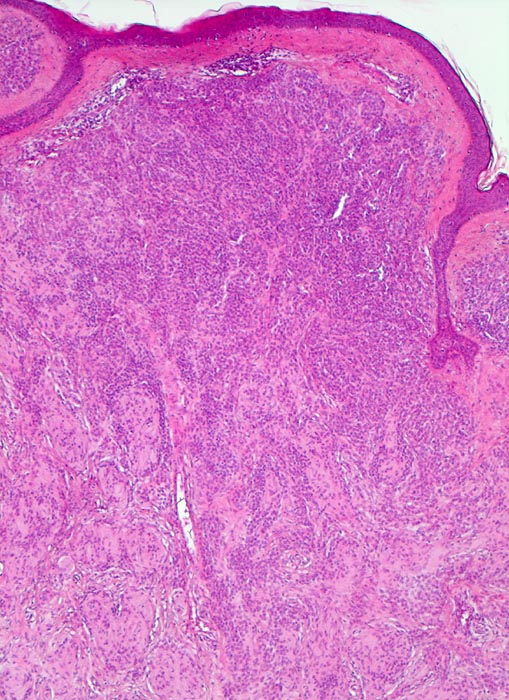

• Symmetrischer leicht exophytischer Tumor.

• Die Tumorzellen bilden Nester in der Epidermis und in der Dermis (=dermoepidermaler bzw. compound Naevus).

• Die oberflächlichen Naevuszellen zeigen reichlich helles, teils pigmentiertes Zytoplasma und helle ovale Kerne mit kleinen, deutlich erkennbaren Nukleolen. Zur Tiefe hin werden die Naevuszellen kleiner, haben weniger Zytoplasma und dunkle kleine Kerne ohne gut erkennbaren Nucleolus. Die Zellnester werden zur Tiefe hin ebenfalls kleiner (=Ausreifung).

• Keine Mitosen, keine Zellatypien.